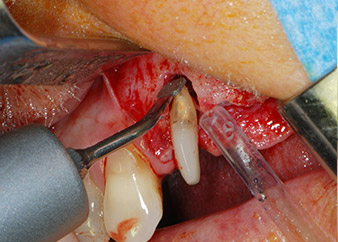

kompletter Verlust von Knochen und Attachment

Abb. 2 und 3: Bei der Freilegung einen Monat nach endodontischer Revision und Beginn einer systematischen Parodontalbehandlung weist die bukkale Wurzel des Zahns 24 einen kompletten Verlust von Knochen und Attachment auf.

Zunächst wurde in einem Versuch, das Paro-Endo-Problem zu lösen, an der verbleibenden Wurzeloberfläche ein vorsichtiges Debridement mit einem piezochirurgischen Gerät vorgenommen (Piezomed, W&H) (Abb. 4); dann wurde der Apex mit dem gleichen Instrument im Sinne einer WSR abgetragen, um das verbleibende infizierte apikale Gewebe zu entfernen (Abb. 5). Eine retrograde Füllung war nicht notwendig, da die orthograde Füllung gerade revidiert worden war.

Brückenpfeiler

Abb. 4: Um den Zahn 24 als vorläufigen Brückenpfeiler zu erhalten, wird das Parodont mit einem piezochirurgischen Sytem gereinigt ...

bukkale Wurzelspitze

Abb. 5 ... und die bukkale Wurzelspitze mit dem gleichen Instrument abgetragen (WSR).